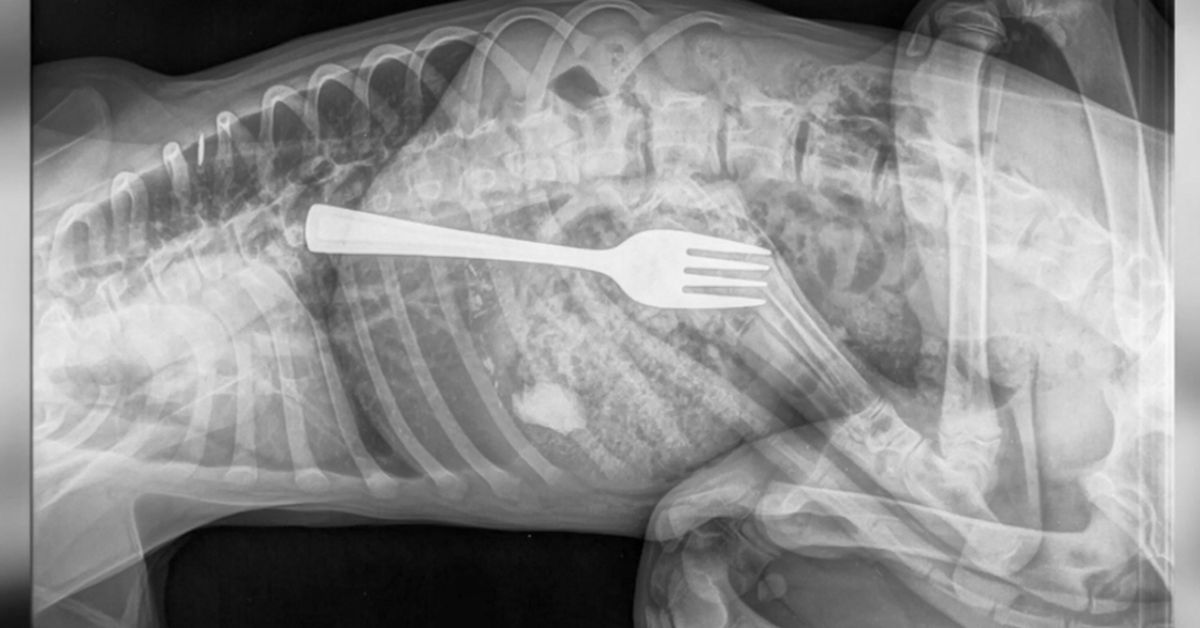

A 5-month-old golden retriever named Dustin has bitten off a little more than he can chew: an entire fork.

Adelaide Animal Emergency & Referral Centre posted on its Facebook page a video of the procedure required to help Dustin remove the silverware from his stomach.

"Now, how does one remove a fork? Option 1: remove via endoscope, OR Option 2: remove via surgical intervention. Lucky for Dustin, option 1 was a success!"